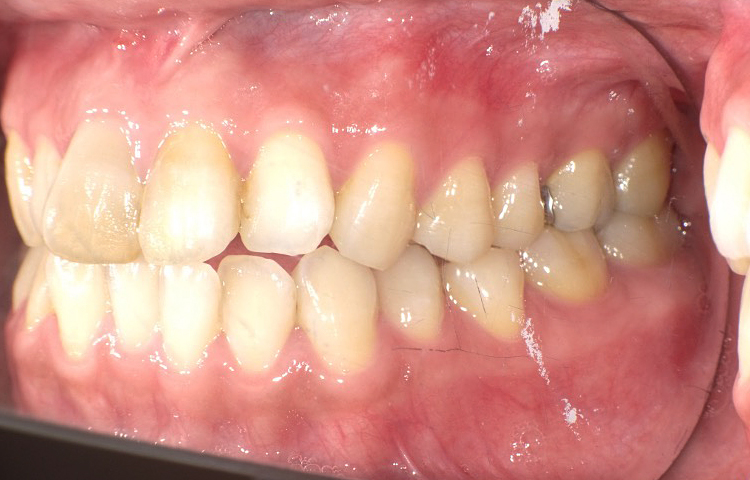

症例3

治療前

治療後

| 主訴 | 上下前歯全体の歯並びが気になる |

|---|---|

| 治療 期間 |

約6ヶ月 |

| 治療費 | 330,000円(税込)/調整費用別途 |

| 治療 内容 |

上下の前歯部にワイヤーを着けて進めていく、プチ矯正で施術。 |

| 治療の リスク |

固定の装置をつけないと後戻りしてしまう。 |